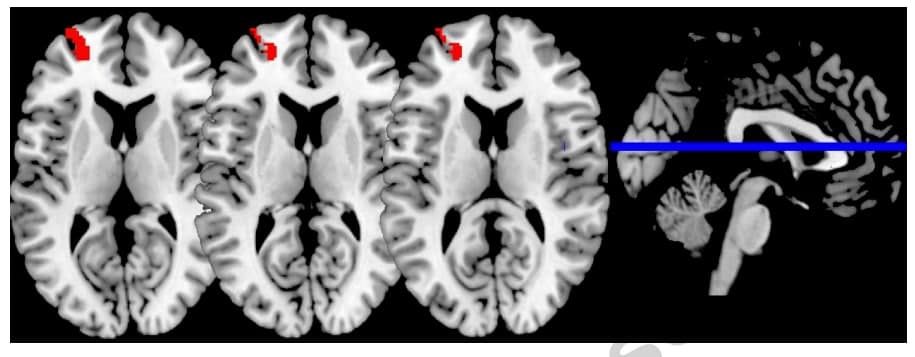

Большой вклад в открытие этих намеков внесла нейрофизиолог Сара Лазар из Гарвардского университета. Еще в начале нулевых она исследовала мозги медитирующих при помощи томографа. Оказалось, что у этих людей больше связей между нейронами в ПФК, чем у среднестатистических американцев. Но то могла быть случайность — совпадение генетической или средовой информации. Поэтому позже она провела другой опыт, в котором показала, что после двух месяцев медитации у обычного человека действительно меняется мозг.

Лазар привлекла 16 человек, которые никогда не медитировали. Поместила их в томограф и сделала контрольный снимок мозга. Затем каждому предложила программу ежедневной медитации осознанности: всего 30-40 минут в день на протяжении восьми недель. По прошествии этого периода всех испытуемых снова обследовали в томографе. Что же увидела Лазар и ее коллеги? Во-первых, увеличенный гиппокамп — область мозга, ответственная за память, обучение и регуляцию эмоций. Во-вторых, уменьшенную миндалину, которую часто связывают с реакцией «бей или беги». Обычно она активируется при стрессе. Интересно, что ее сокращение коррелировало с оценкой самих испытуемых. Те отмечали сниженный уровень стресса после двухмесячного курса.

На снимке указана зона миндалины, которая уменьшилась после эксперимента

Схожие результаты демонстрировали и другие независимые исследования. Например, канадские психологи из Монреальского университета показали, что миндалина может уменьшиться и после одной недели ежедневных 20-минутных занятий. Даже такого короткого срока достаточно, чтобы снизить ее активность в ответ на негативные картинки с насилием или жертвами катастроф. О такой тенденции говорят и метаисследования.

Эксперимент длился три дня, а результаты оценивали по снимкам МРТ до и после упражнений и забору крови, который показывал уровень интерлейкина 6 (IL-6) — провоспалительного цитокина. У медитировавших участников, в отличие от группы релаксации, уровень IL-6 значительно снизился уже через три дня интенсивных тренировок. Также в их дорсолатеральной префронтальной коре (ПФК), которая отвечает за сдерживание любых приятных, но вредных для организма порывов (вроде лишней булочки перед сном), образовалось много новых связей, чего не наблюдалось у испытуемых из первой группы.

Образование новых связей в ПФК